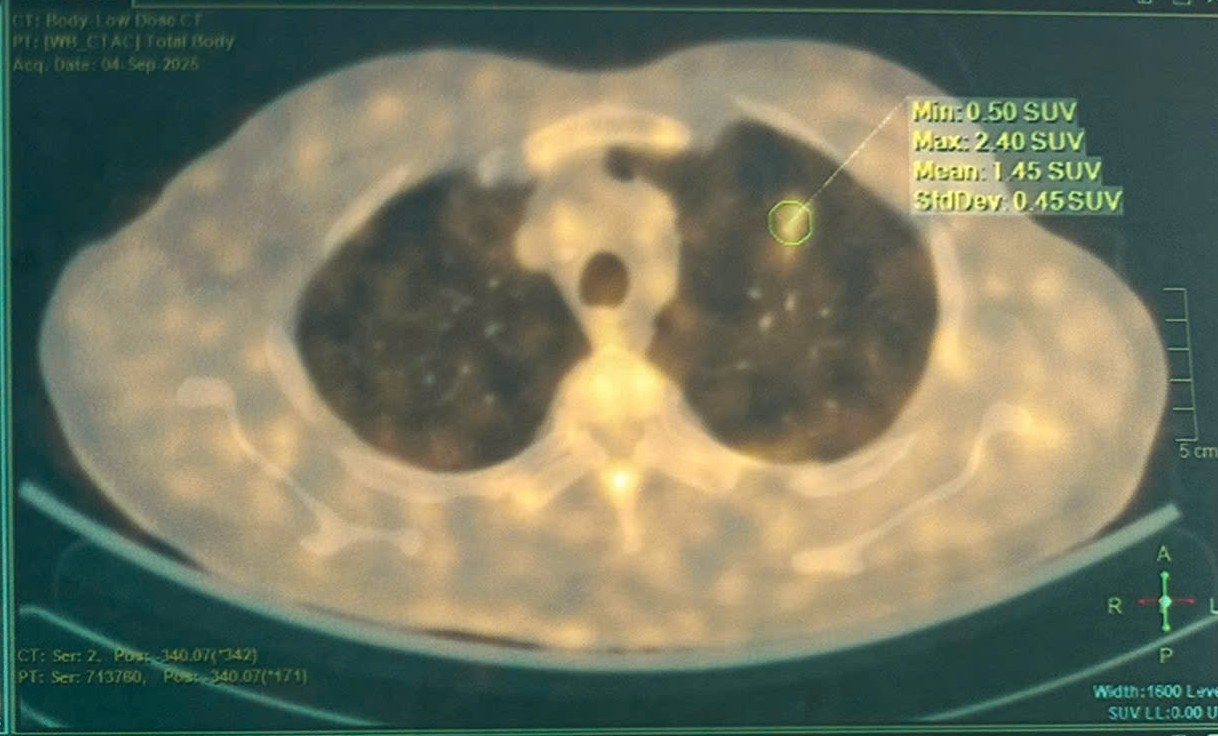

PET/CT:

Hình 4: Hình ảnh vài đám tổn thương dạng kính mờ bờ tua gai ở thùy trên phổi trái, lớn nhất kích thước 17×17 mm, tăng nhẹ hấp thu FDG (SUVmax: 2.4) – Theo dõi do viêm.